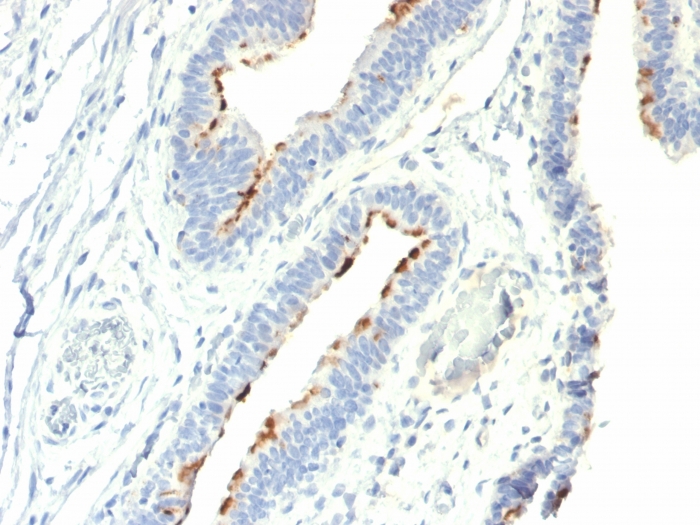

Recognizes a disaccharide epitope, Gal � �1-3GalNAc, of Thomsen-Friedenreich (TF) antigen. It is specific for both anomeric forms of the disaccharide (TF and TF � �, including related structures on the glycolipid) and shows no cross-reactivity with sialylated glycophorin. The Thomsen-Friedenreich antigen acts as an oncofetal antigen, with low expression in normal adult tissues but increasing to fetal levels of expression in hyperplasia or malignancy. It is considered as a pan-carcinoma marker. This MAb is capable to agglutinate desialylated red blood cells. During metastasis, the ability of malignant cells to form multicellular aggregates via homotypic or heterotypic aggregation and their adhesion to the endothelium are critical. The tumor-associated carbohydrate Thomsen-Friedenreich antigen (Gal-GalNAc) is involved in tumor cell adhesion and tissue invasion. It also causes an immune response, and overexpression of the antigen causes cancer cells to be more sensitive to natural killer cell lysis. The Thomsen-Friedenreich antigen is suppressed in normal healthy cells and represents one of the few chemically well-defined antigens associated with tumor malignancy. The presence of the Thomsen-Friedenreich antigen on the surface of cancer cells may result from a divergence from the normal pathway for O-linked glycosylation in these cells, most likely caused by inappropriate localization of the enzymes involved in synthesis of the disaccharide.

KG1 cells or human colorectal carcinoma tissues.